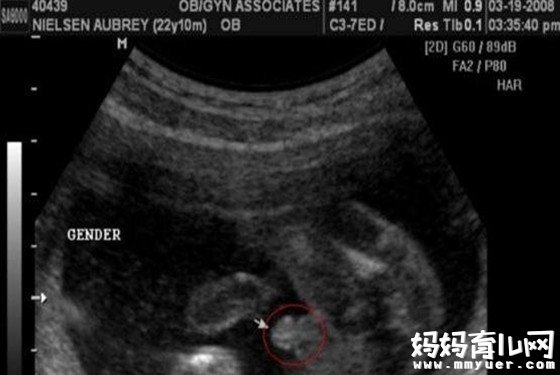

第一种:在彩超单上会印,顶头最右边有两行字,是英文字母和数字组成的,第一行是日期,第二行是时间,如果第一行是M开头,那就是male男,如果是F开头就是female女,第二行打头的T是时间的意思。

第三种:通过四维彩超图看清胎儿性别

男宝宝B超图

"凸出的东西"是他的标记:你们看到圆圆的是DANDAN,如果看到圆圆的加小肠的就是全部JJ